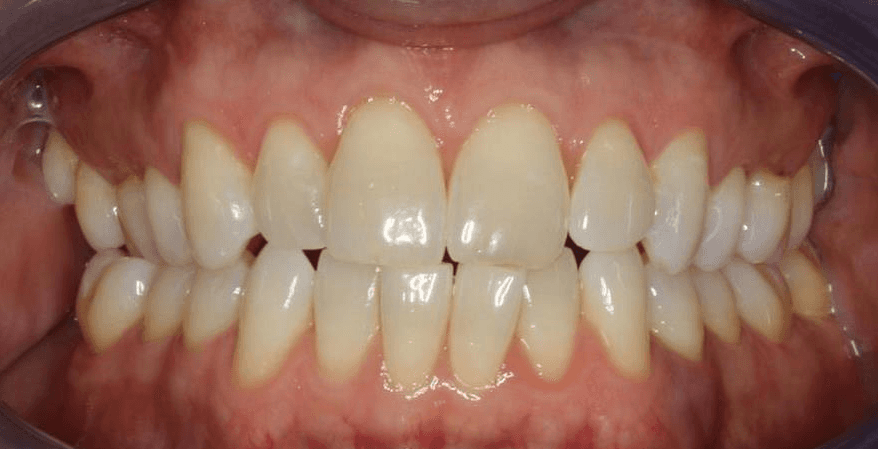

Diganosis: Minor and moderate crowding, anterior open bite, reverse smile arc, narrow maxilla, crossbite, tapered arch form

Adjuncts: Class III elastics, attachments, IPR

Final results

INTRAORAL